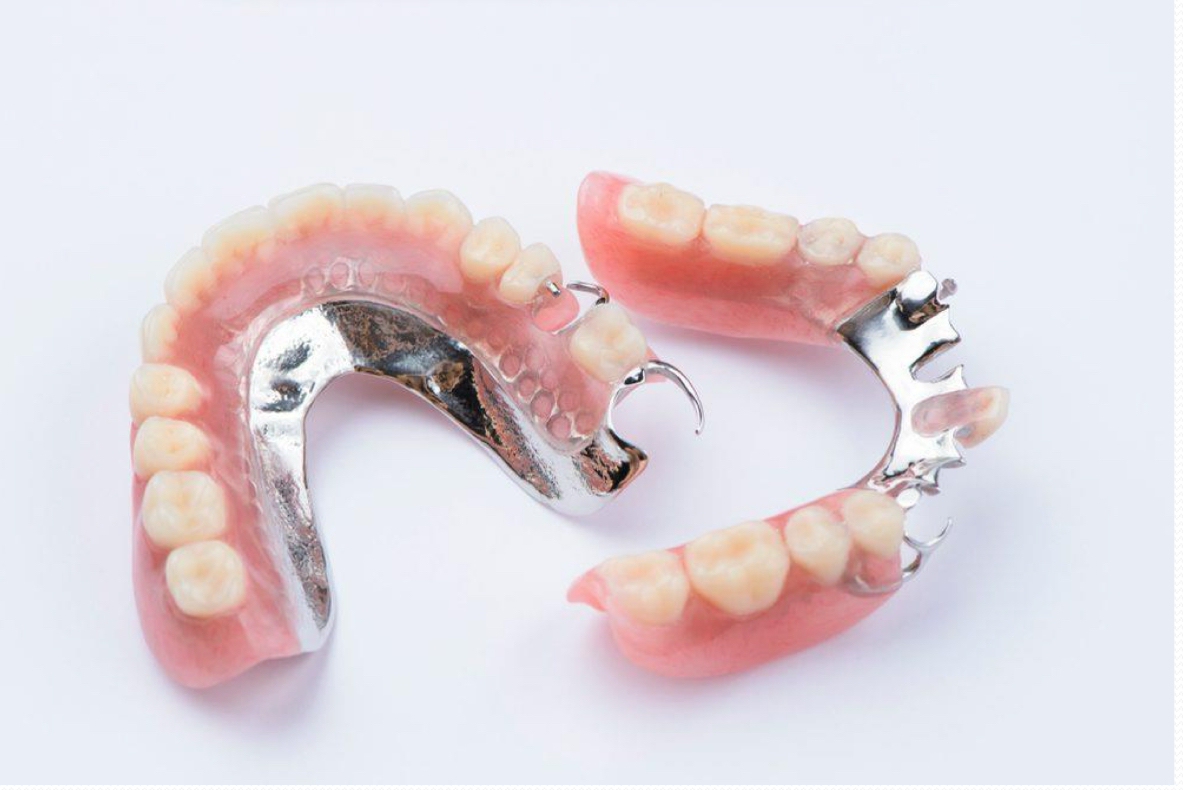

Removable partial denture

Acrylic denture

Base material

Metallic pins